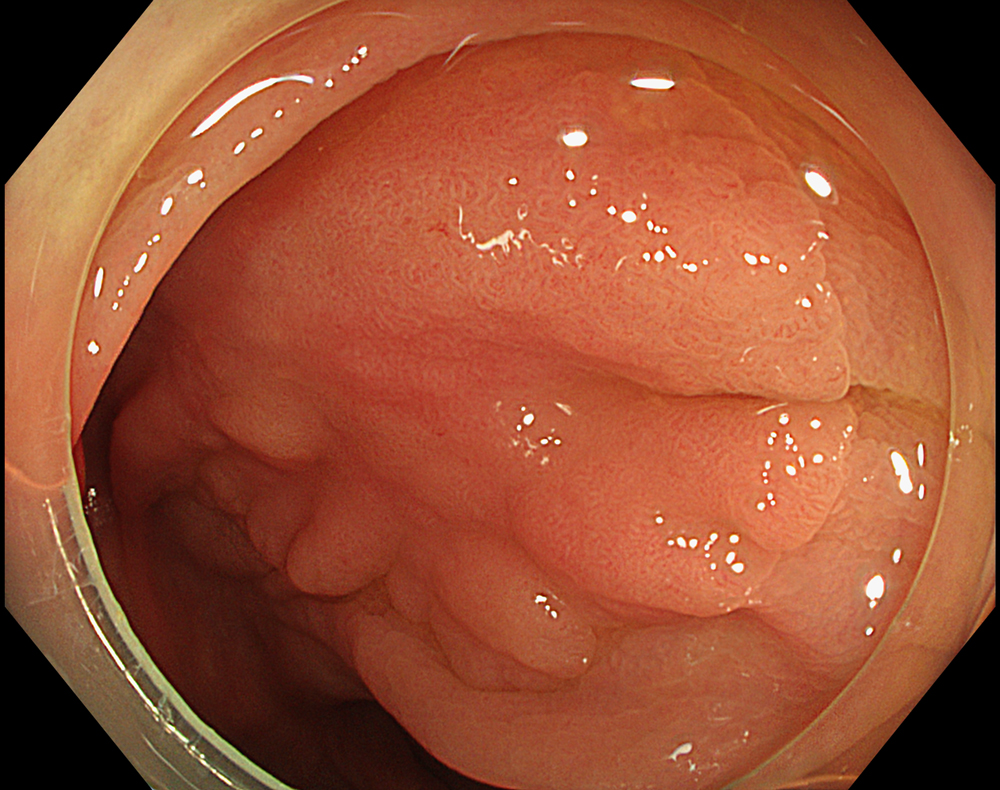

1. LST-NG in WLI

A 30-mm non-granular laterally spreading tumor (LST-NG-FE) located at the hepatic flexure is observed as a flat elevated lesion on white light imaging.